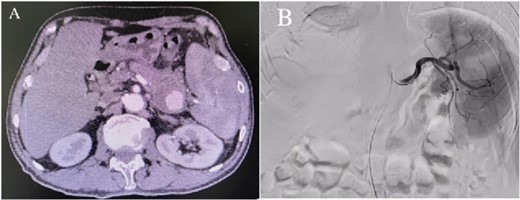

Enhanced CT showed regional portal hypertension and CP invading the splenic artery and forming a pseudoaneurysm of the splenic artery, partially invading the jejunum (Fig. 1A). Subsequent celiac angiography confirmed a pseudoaneurysm originating from the splenic artery (Fig. 1B). Combined with the characteristics of the patient’s history and the results of angiography, the patient was diagnosed with gastrointestinal bleeding: pseudoaneurysm of the splenic artery and CP. After excluding relevant contraindications, abdominal arteriography and embolization were performed simultaneously. So further intubation until confirmation of splenic artery angiography, we used a coil to embolize the pseudoaneurysm. At that time, repeat angiography showed that the main splenic artery and the pseudoaneurysm showed no further enhancement (Fig. 2B). Subsequent CT scan 6 days after the embolization showed no filling of the pseudoaneurysm (Fig. 2A), and he was discharged 2 days later. After 6 months of follow-up, the patient recovered well and returned to normal work and life.

(A) Abdominal CT scan 6 days after the embolization showed no filling of the pseudoaneurysm. (B) After embolization, re-examination showed that the main trunk of the splenic artery was accurately occluded, and the staining of the pseudoaneurysm of the splenic artery disappeared.